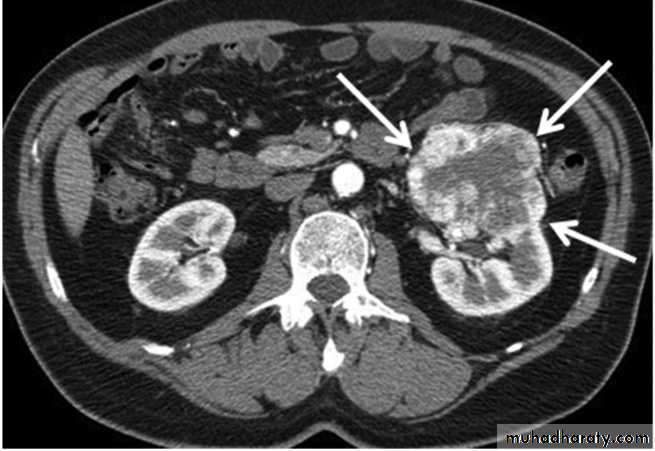

• Renal cell carcinoma

• It represent 80-90% of all renal malignancy, peak age 55 year. It is bilateral in 2%. It metastasize to the lung, liver, bone(lytic expansile), regional LN, and adrenal glands• US: solitary mass bulging from the renal outline. It is usually iso- or hypoechoic compared to normal kidney. Most show some heterogeneity. It is of irregular outline. Necrosis will give areas of low echogenicity in the centre of large tumors.

• CT: spherical mass, often lobulated, usually isodense or hypodense compared to normal renal tissue, occasionally hyperdense. They enhance variably with intravenous contrast but almost always less than normal renal tissue. About 1/3 have calcifications.

• CT is the current method of choice for staging of RCC because:

• 1.it show the local direct spread

• 2.can demonstrate enlargement of drainage LN

• 3.show tumor growing along the renal vein into IVC.

• 4.diagnose liver, adrenal and pancreatic metastases